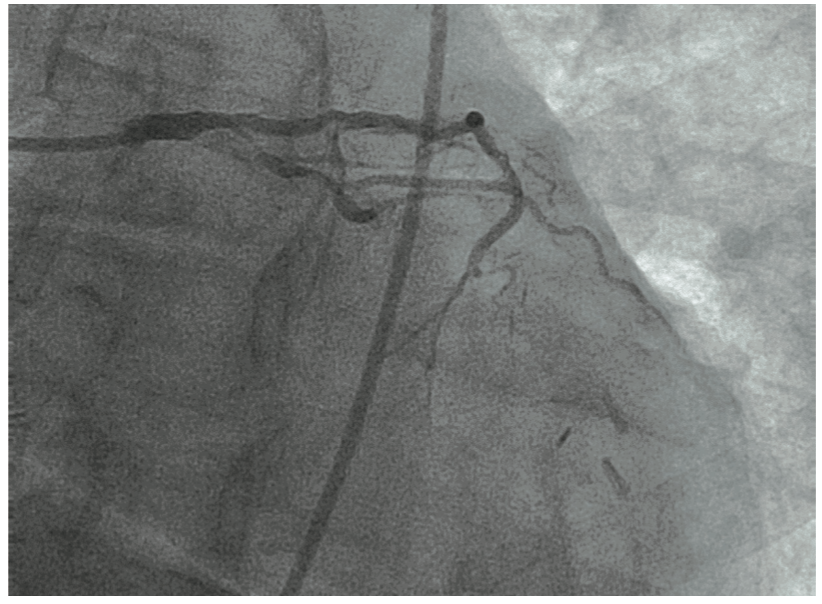

A diagnostic right heart catheterization revealed high Fick cardiac output/cardiac index, severe pulmonary hypertension (70/27, [40 mmHg]), moderate to severely elevated left-sided filling pressures (left ventricular end-diastolic pressure [LVEDP] 28 mmHg), pulmonary capillary wedge pressure (24 with V-waves to 40 mmHg), and moderately elevated right-sided filling pressures. A diagnostic left heart catheterization revealed severe, multivessel native CAD. Bypass graft anatomy revealed severe graft disease in the ostial LIMA to LAD (80% stenosis with moderate-severe calcification; Figure 1A, Video 1) and mid-distal SVG to OM2-OM3 (mid 80%, distal 99% diffuse stenosis, thrombus, diffuse calcification; Figure 2).

Video 1. Coronary angiogram showing severe stenosis with eccentric, focal calcification at the LIMA ostium.

There was also mild to moderate non-obstructive disease of the SVG to the right PDA. The ostial LIMA lesion was validated with the administration of intracoronary nitroglycerin and later with intravascular ultrasound (IVUS) (Figure 1B), as well as by the observation of severe balloon compression during the interventional procedure, as described below.